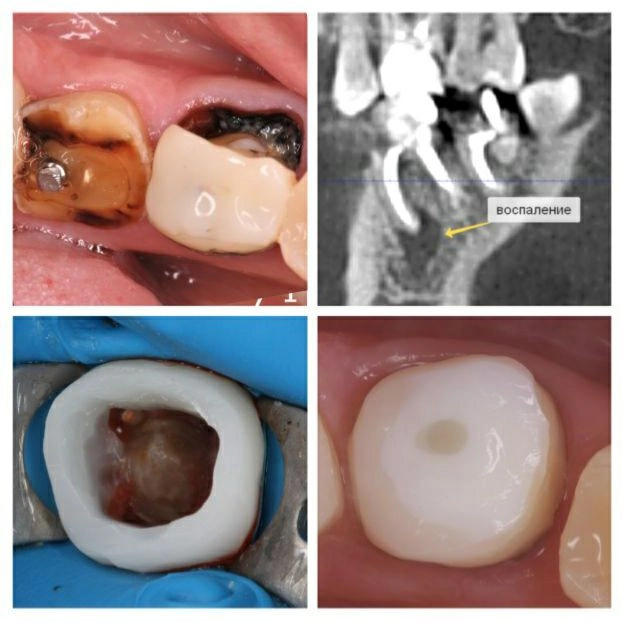

Те самые Russian Red Tooth, которые окрашиваются после лечения резорцин-формалиновым методом.

Цвет может быть от розового до красно-коричневого.

Пациентка обратилась за перелечиванием "шестерки" и "семерки", т.к. ей предстояло ортодонтическое лечение.

• В седьмом зубе — пропущен один канал и стоит большой анкерный штифт.

Его надо извлекать предельно аккуратно, чтобы не повредить корни.

• В обоих зубах "кисты".

Что сделано?

✔️Старые пломбы убраны;

✔️Извлекли анкерный штифт;

✔️Нашли и пролечили все каналы;

✔️Заложили лекарство для лечения воспаления;

✔️Зубы восстановили;

✔️Закрыли временной пломбой, смотрим за динамикой заживления "кист".

Далее пациентку направляем к ортодонту.